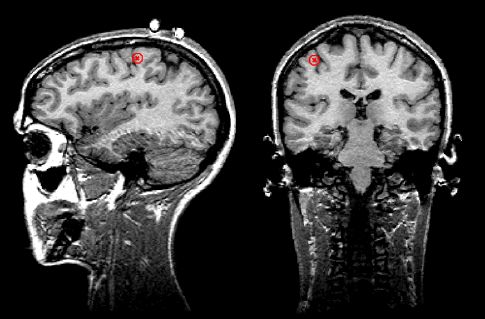

Нужно отметить, что этап наложения электродов остается наиболее трудоемким при проведении ЭЭГ – исследований, он практически не поддается автоматизации и требует участия опытного квалифицированного специалиста. Перспективным направлением решения этих проблемм является метод магнитоэнцефалографии (МЭГ). В нем используются магнитные, а не электрические поля (как при ЭЭГ). МЭГ определяет направление аномальной электрической активности мозга, а не только усиливает сигналы. Многие ученые считают, что МЭГ дополняет ЭЭГ, но его применение в основном пока ограничивается исследовательскими целями [7] (рис.15).

Рис. 15. a) Нейромагнитоэнцефалограф и б) -г) Современные способы представления результатов исследований с помощью ЭВМ (с сайтов http://ntl-cbm.narod.ru/MEG-SITE/index-meg.htm и http://jenameg10.meg.uni-jena.de/gallery.htm)

Согласно современным врачебным стандартам, время, затраченное врачом на анализ и описание результатов в ходе типового ЭЭГ исследования сравнимо со временем, требующимся для регистрации ЭЭГ, включая подготовку пациента, установку электродов, собственно запись и пр. Еще бы, врачу зачастую приходится анализировать одновременные записи нескольких десятков сигналов. Очевидно, что удобство представления информации является одним из важнейших факторов, влияющих на время проведения исследования и правильность интерпретации результатов. Тут неоценимую помощь энцефалографисту предоставляют современные ЭВМ. Например, в программном обеспечении, поставляемым с большинством современных энцефалографов присутствуют средства топографического картирования, в том числе при трехмерной визуализации [1, стр 141]. При таком картировании различными оттенками цвета отображаются амплитудно-частотные свойства сигналов во всех используемых отведениях в любой момент времени непосредственно на схематическом изображеннии головы человека как, например, на рис. 15 б, г.